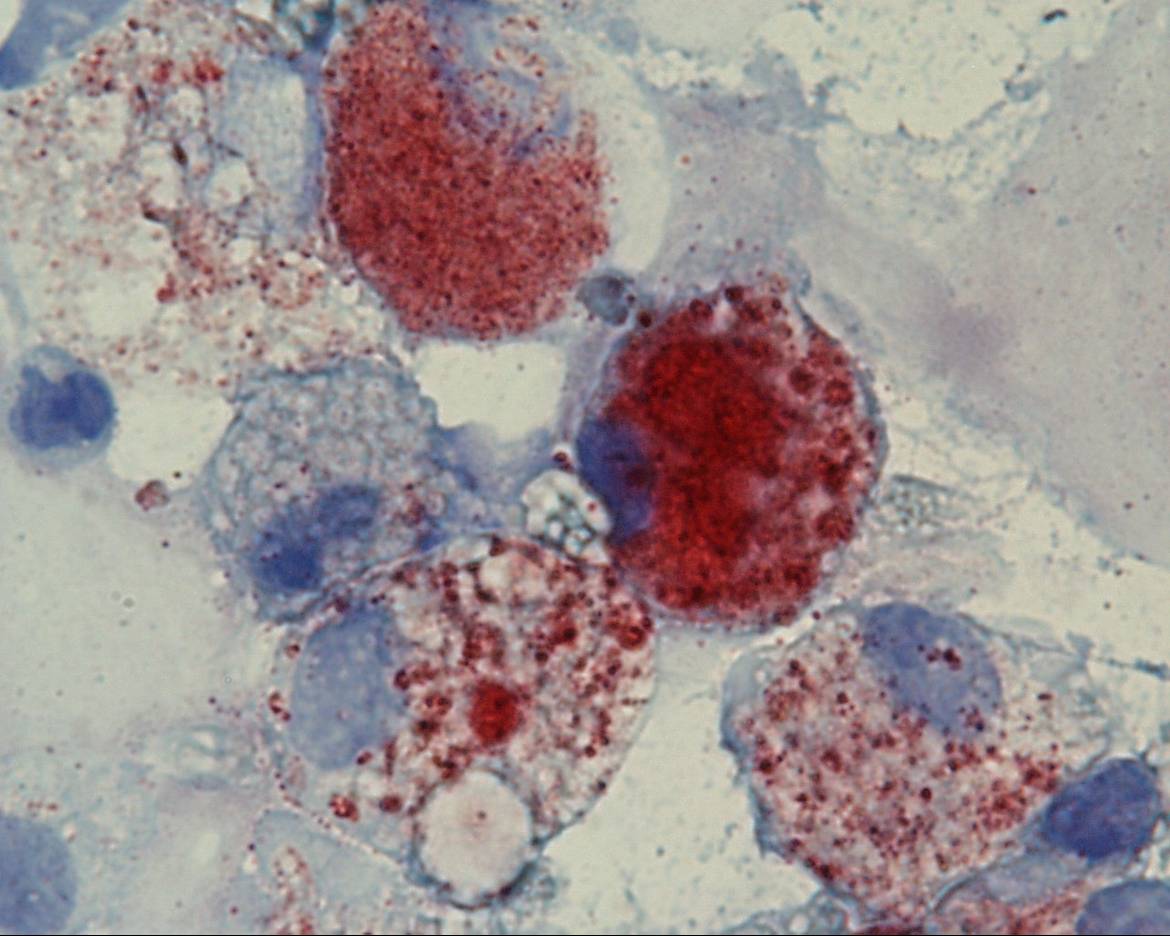

The patient underwent bronchoscopy and bronchoalveolar lavage (BAL) was performed. BAL fluid (BALF) was analyzed using different procedures. Diff Quick staining showed foamy marophages and cocci (Figure 3) that appeared to be Neisseria Meningitidis at microbiological culture (Figure 4). The staining “Oil Red –O” -specific for mineral oils and lipids- depicted the optically empty vacuoles (Figure 5).

Figure 5 ORO staining of BAL fluid : lipid laden macrophages.

Discussion ACS has a great impact on people affected by sickle cell anemia: 50% of patients experience at least one episode of ACS in their life; older patients have more severe episodes [3]. Pulmonary fat embolism from bone marrow infarction and infections are frequent cause of ACS [1]. BAL hallmarks in ACS are: presence of macrophages containing optically empty vacuoles in their cytoplasm and –not constantly- presence of bacteria. Optically empty vacuoles are well stained with specific products identifying lipids. Microbiological investigations are useful to better define the nature of microorganisms. FBS is an useful tool in the suspect of acute chest syndrome since analysis of BAL fluid may be useful for a precise clinical work-up in patients with this syndrome.